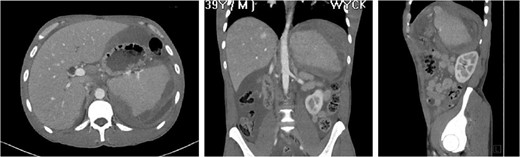

The ‘Islands’ of preserved spleen lit up with IV contrast surrounded by a large collection of old blood and devitalized tissue.

Our patient was vaccinated given that post-procedure CT showed the spleen to be partially necrotic with only two islands of well-perfused, preserved spleen depicting >15% decrease in splenic volume. The plan was to perform interval splenectomy however he was lost to follow up.